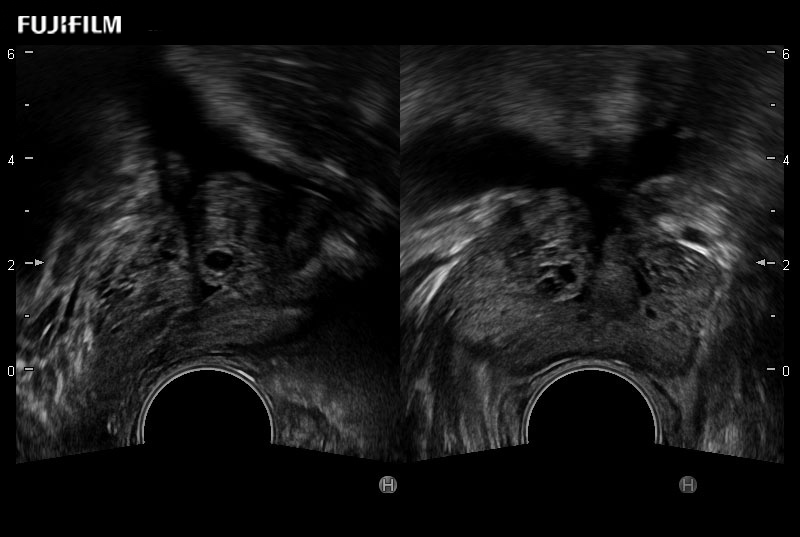

Provides real-time imaging of both the sagittal and transverse planes

Main Specifications: